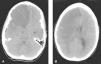

A) Angiorresonancia de polígono de Willis. Alteración de señal en arteria cerebral media derecha, con escasa señal en la división silviana y marcada irregularidad mural y menor señal respecto a la homónima contralateral. B) TC craneal tras reposición ósea. Degeneración quístico-necrótica con tracción ventricular homolateral en relación con la pérdida de volumen parenquimatosa hemisférica derecha. Poroencefalia evolucionada secundaria al infarto derecho de arterias cerebrales media y anterior derechas.

La evolución posterior ha sido favorable. Siete meses después se realizó la reposición ósea sin incidencias (fig. 2B). Tras 18 meses, presenta una puntuación de 3 en la escala pediátrica de ictus del National Institute of Health (NIHSSPed) (rango de 0 a 42), a expensas de la afectación del campo visual periférico. Está escolarizado con aceptables resultados académicos. Capacidad de deambulación con hemiparesia leve. Autonomía para la alimentación y cuidado personal.